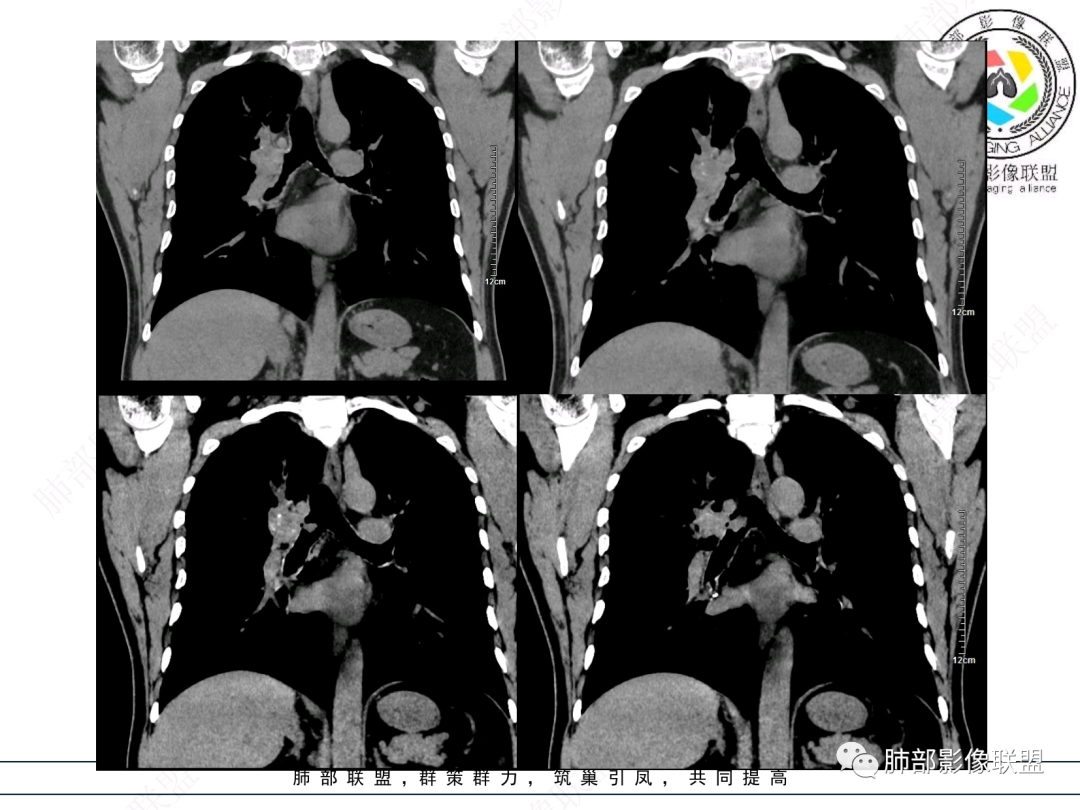

这个病例比较好,我们的观察点在哪?这是右上叶支气管病变,需要了解:腔内、壁、腔外、远端,腔内有软组织密度影,近端膨隆。

红色:软骨连续性良好,壁外有软组织密度影,绿色:软骨不连续,破坏了,外面软组织密度影。

南边:提示软骨破坏,也就是病灶腔内朝壁外侵犯了——恶性。

远端支气管腔内不强化的是粘液栓,强化的是肿瘤。

如果在这种情况下临床想通过CT了解啥?主要是:a、与附近结构的关系:血管、淋巴结;b、远端情况;c、其他区域转移情况;

影像上分析的观察点:腔内、壁、腔外、远端,然后就是远端肺组织、淋巴结、肺血管、胸膜、其他肺部,这个人就是阻塞性炎症为主。